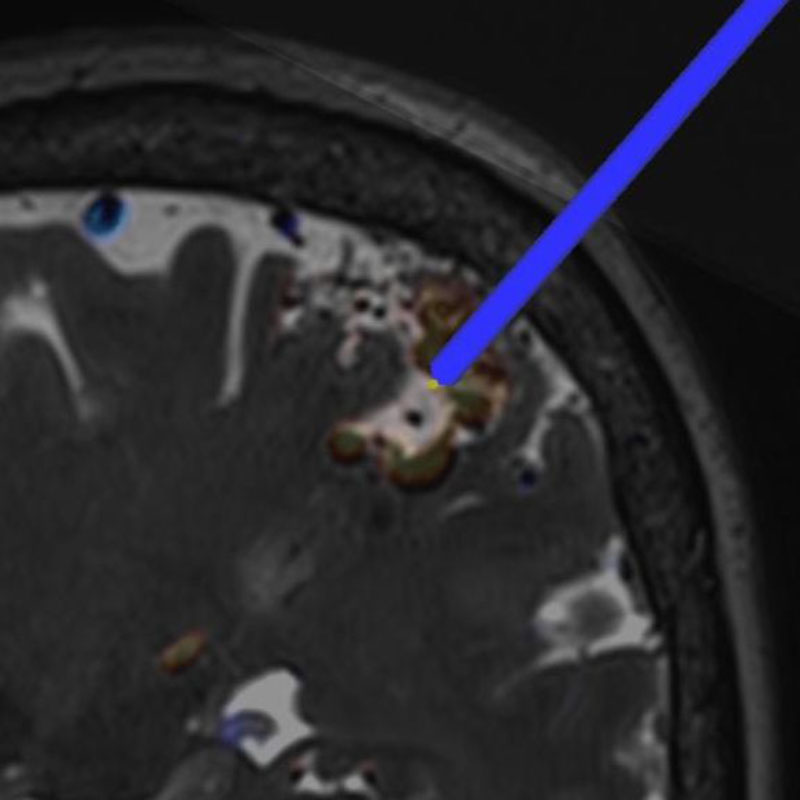

No.359 モニタリング

No.359 手術前

No.359 手術中

No.359 手術後

出血既往があり。2回の手術前血管内手術の後に、

Lateral transpeduncular approachにより再々出血予防を目的に

摘出手術を行う。完全摘出であることを確認した。

手術による合併症や後遺症なしで退院した。経過良好。